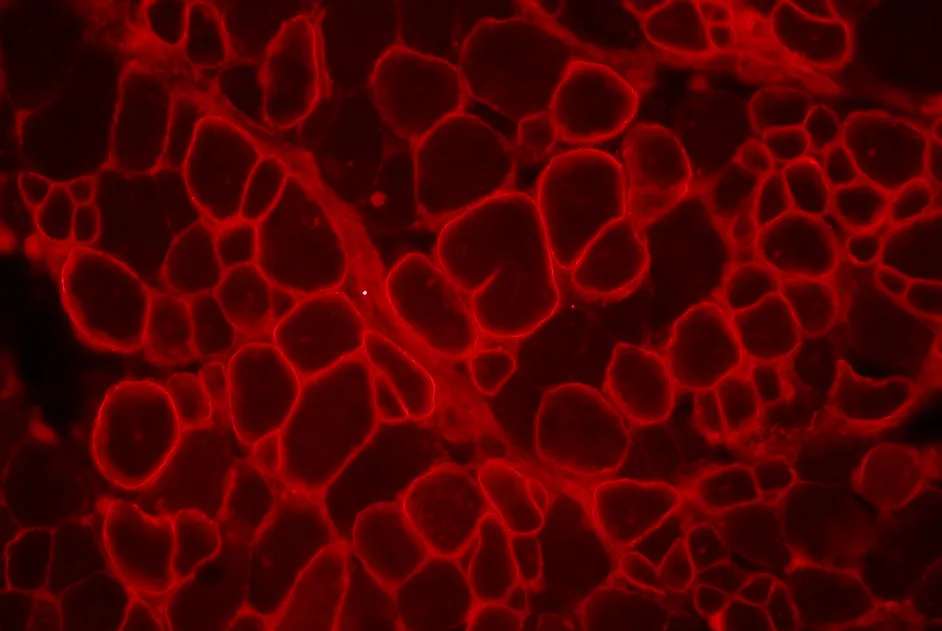

La laminine 211 est une protéine qui contribue au lien mécanique entre la fibre musculaire et la matrice extracellulaire qui l’entoure. Elle est constituée de 3 sous unités : α2, β1 et γ1. La sous-unité α2 est codée par le gène LAMA2, déficient dans la DMC1A. Dans cette maladie, en l’absence de laminine α2, la laminine 211 est « remplacée » par la laminine 411, une autre laminine, qui, sans sous-unité α2, ne solidarise pas aussi bien la cellule musculaire à la matrice extracellulaire.

L’approche mise au point par le Pr Rüegg du Biozentrum, soutenu par l’AFM-Téléthon, consiste à utiliser deux petites protéines dites « connectrices » qui, en se connectant à la laminine 411, permettent de rétablir un lien avec la matrice extracellulaire. L’expression de ces protéines dans des souris déficientes en laminine α2 a permis de restaurer la structure et la fonction du muscle de ces modèles de DMC1A.